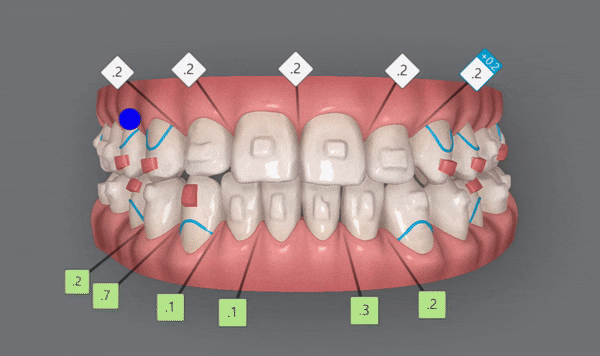

4th(11개)

네번쩨 클린체크를 끝으로

정말 디테일한 부분까지 상호보완, 개선하여

좀더 섬세한 작업을 통해 마무리를 해드렸습니다 ^^

전체적으로 위,아랫니들이

제 위치를 찾으며 정리가 되었습니다!!

어금니들의 대이동이 끝이나고

클린체크의 예상대로 교정 마무리가 잘 되었어요!!

윗니와 아랫니 사이의 틈이 사라지고,

윗니를 덮고 있던 아랫니들이 제 위치를 찾으며 부정교합이 개선되었을 뿐만 아니라

정중앙선이 일치하도록 마무리 해드렸습니다 :)